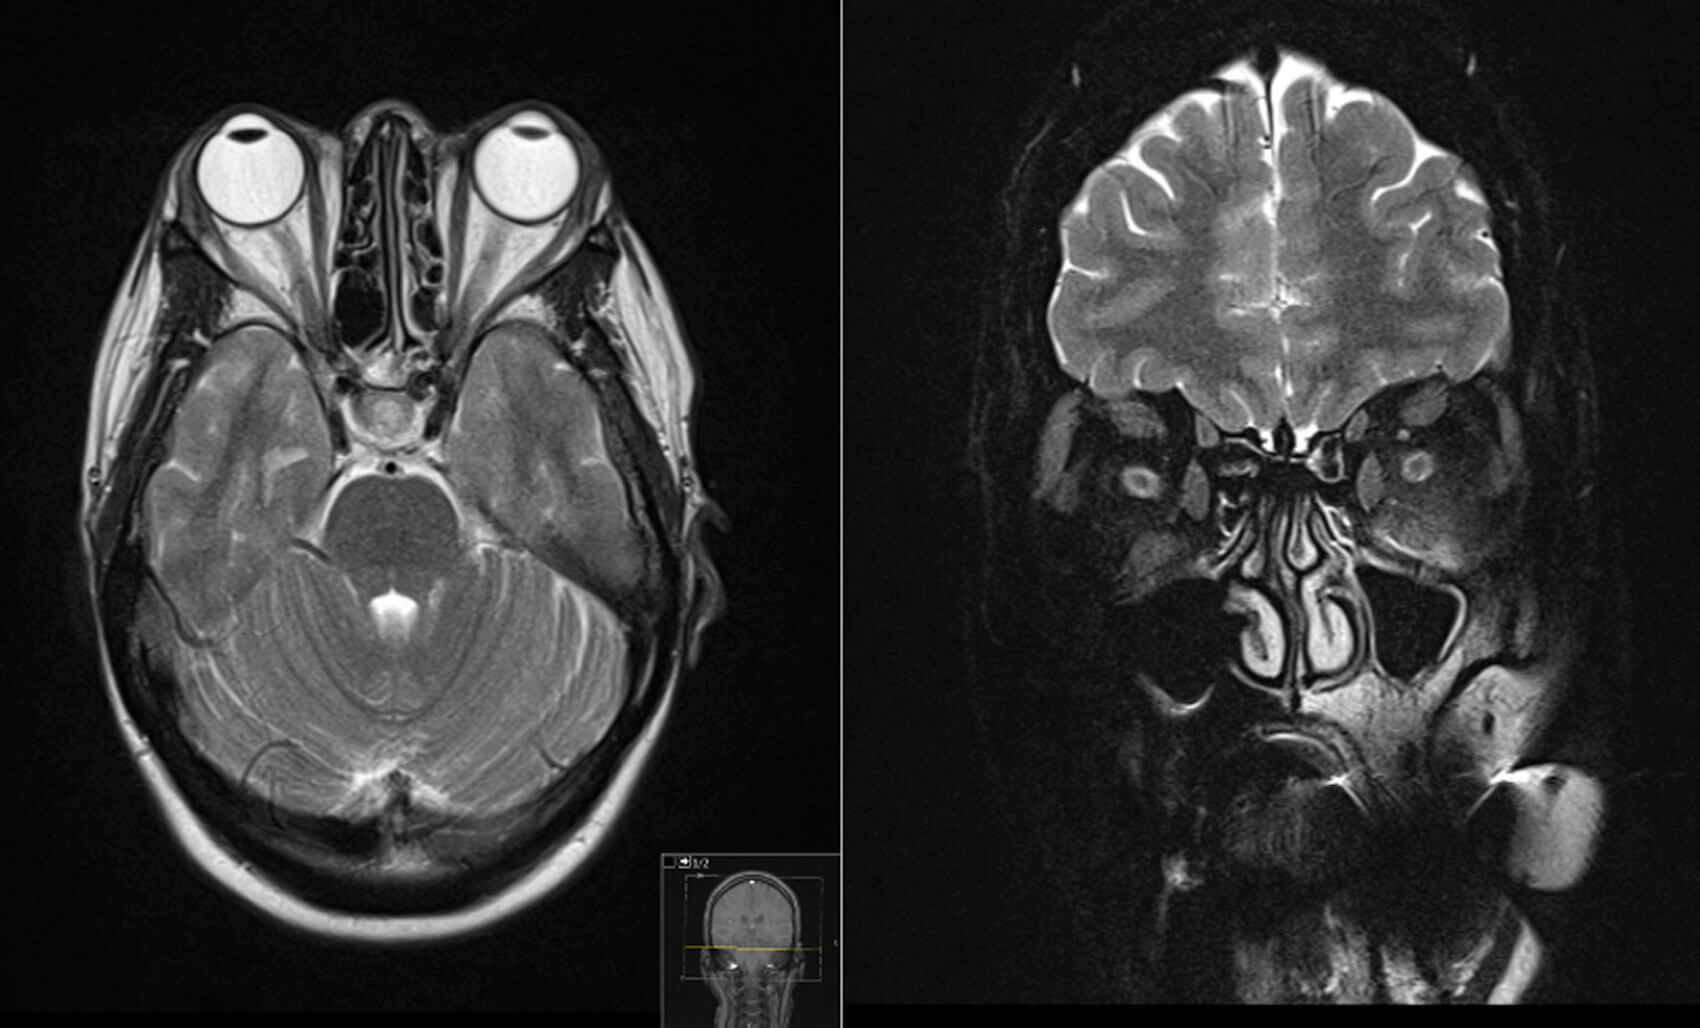

Imaging studies of the orbit such as ultrasound, computed tomography (CT) and magnetic resonance imaging (MRI) can help confirm TED whilst excluding other differential diagnoses. CT without contrast is most popular as it shows bony anatomy of the orbit and is more cost effective compared to MRI. CT orbits can show you characteristic TED changes such as enlargement of the extraocular muscle bellies and sparing of the tendons. Typically, there is asymmetrical bilateral involvement of the extraocular muscles affected in the following pattern: inferior recti, medial recti, superior recti, lateral recti and the obliques. If compressive optic neuropathy from orbital apex crowding is suspected, MRI is the gold standard imaging choice [14].

Figure 1: MRI orbit showing bilateral proptosis. There is associated thickening of the inferior, superior and medial extra ocular muscles. There is sparing of the lateral extraocular muscles bilaterally. There is minor high-signal associated with the left inferior rectus muscle. There is increase in the volume of the intra and extraconal fat bilaterally. Limited views of the intracranial contents are within normal limits.